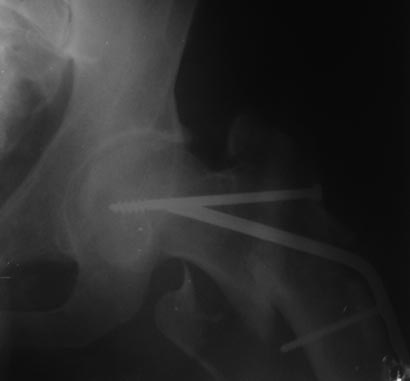

Имя     : 3 лПОФТПМШ 16.01.2013.jpg

Тип     : image/jpeg

Размер  : 28719 байтов

Описание: отсутствует

Url     : http://weborto.net:8080/pipermail/ortho/attachments/20130121/1122b3fc/attachment-0007.jpg